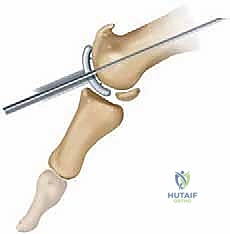

2. إيثاق المفصل (Arthrodesis / Joint Fusion)

- لمن تصلح؟ المراحل المتقدمة (3 و 4) حيث يكون الغضروف قد تدمر تماماً.

- ما هي؟ الإجراء "الذهبي التقليدي" لتخفيف الألم. يتم إزالة الغضروف المتبقي، وتثبيت عظام المفصل معاً باستخدام مسامير أو شرائح معدنية حتى تلتحم العظام وتصبح عظمة واحدة صلبة.

- العيوب: يقضي على الألم بنسبة 100%، ولكنه يقضي على حركة المفصل تماماً. المريض لن يتمكن من ثني إبهامه أبداً، مما يمنع الجري السريع، القرفصاء، وارتداء أحذية الكعب العالي.

3. استبدال المفصل (Arthroplasty) - الثورة الطبية

- لمن تصلح؟ للمرضى في المراحل المتقدمة (2، 3، وأحياناً 4) الذين يرفضون دمج المفصل ويرغبون بشدة في الحفاظ على حركة المفصل.

- ما هي؟ استبدال أسطح المفصل التالفة بمواد صناعية. وهنا تبرز التقنية الأحدث والأكثر نجاحاً عالمياً: **تقنية Arthrosurface